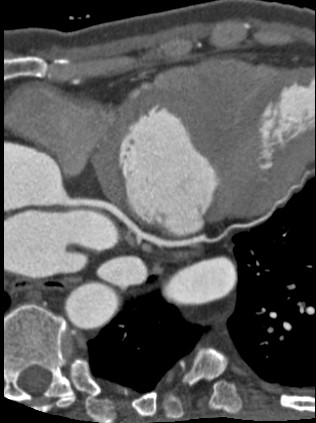

标题: CT24400:患者54岁,心前区不适进行心脏冠脉造影检查。 [打印本页]

标题: CT24400:患者54岁,心前区不适进行心脏冠脉造影检查。

患者54岁,心前区不适进行心脏冠脉造影检查。高手看看有问题没有?